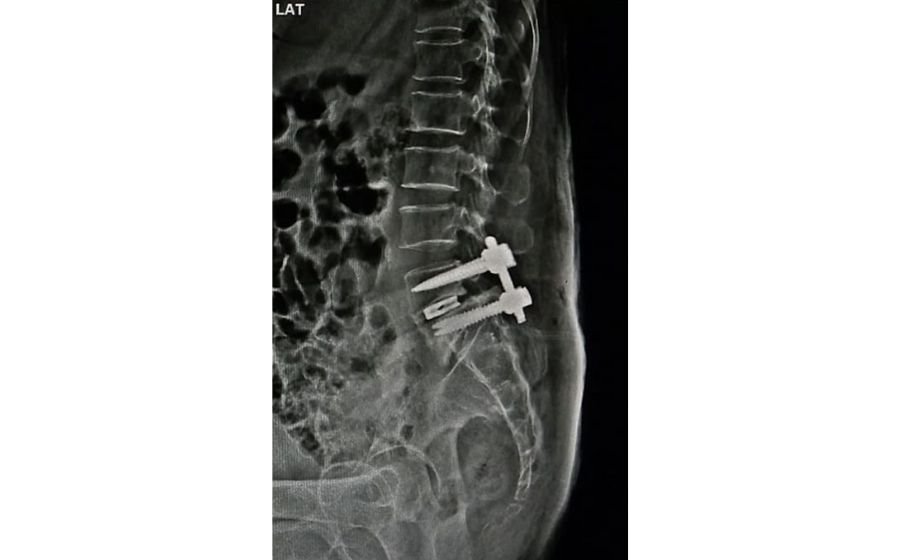

TLIF (Transforaminal Lumbar Interbody Fusion)

TLIF is a minimally invasive fusion procedure used to treat instability, severe disc degeneration, or nerve compression in the lower back. Through a small approach from one side, the damaged disc is removed and replaced with a cage to restore height and alignment. Screws and rods are added to stabilize the spine while it fuses. TLIF helps relieve leg pain, corrects instability, and provides long-term support for improved mobility and daily function.